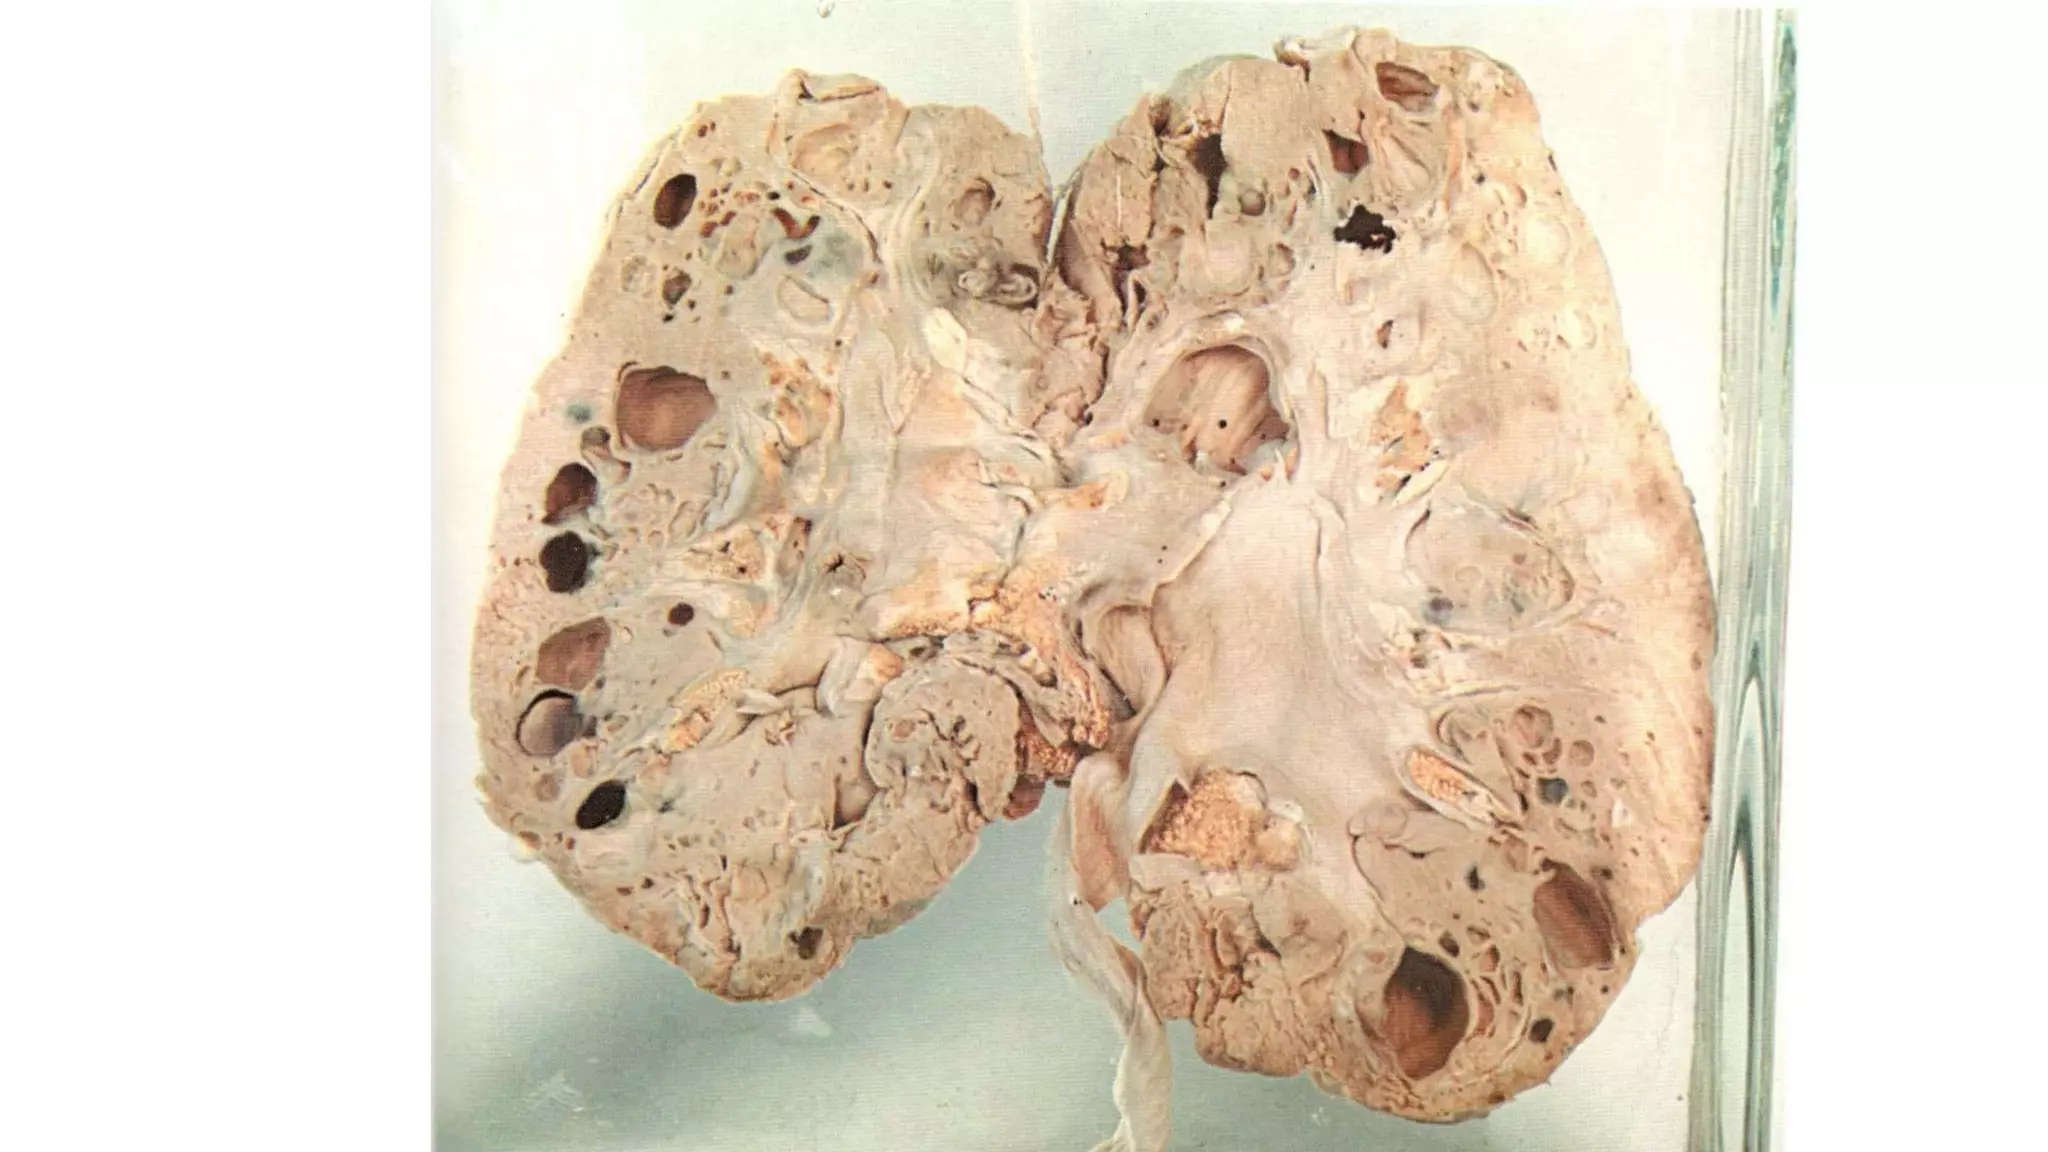

Morphology

o GROSSLY: (JAR)***

 The kidneys are small, symmetrically contracted with diffusely granular external

surface.

 Cut sections, the cortex is narrow and atrophic cannot differentiate from renal

medulla with formation of multiple small cysts (honey-comb appearance)